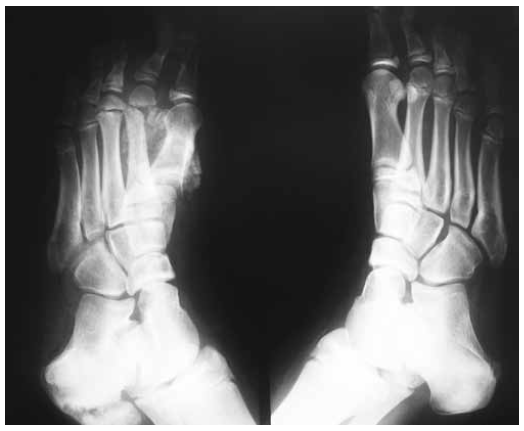

(gffc) german consensus on operative treatment of charcot neuroarthropathy: Introduction to address midfoot instability of charcot disease a promising intramedullary implant has recently been developed to allow for an arthrodesis of the bones of the medial foot column in an anatomic position. Artsen begon voor het eerst deze voorwaarde te identificeren in de jaren 1700. In die tijd leefden mensen met diabetes niet lang, omdat er nog … When neuropathy is present, the bones in the foot become weakened and can fracture easily, even without there being any major trauma. Patients may experience fractures and dislocations of bones and joints with minimal or no known trauma. Problems classification of serveral cn'sof different location different course of cn in correlation to different types of pnp? Correct diagnosis and differentiation from osteomyelitis of the foot and ankle are critical to guide treatment.

Die genaue ursache für die erkrankung ist bisher nicht bekannt. Florin ramadani (kosovo) education and training. Diese wurde erstmals 1888 von jean martin charcot als manifestation der lues beschrieben. Ein beitrag der ag charcot der gesellschaft für fußchirurgie e.v. Introduction to address midfoot instability of charcot disease a promising intramedullary implant has recently been developed to allow for an arthrodesis of the bones of the medial foot column in an anatomic position. 95 % prozent aller patienten sind diabetiker. When neuropathy is present, the bones in the foot become weakened and can fracture easily, even without there being any major trauma. Patients may experience fractures and dislocations of bones and joints with minimal or no known trauma. 3rd foot and ankle symposium arthritic disorders of the foot and ankle diagnosis and management uniklinik balgrist september 9th, 2011 Also called charcot joint or neuropathic joint, charcot arthropathy is a progressive condition of the musculoskeletal system that is characterized by joint dislocations, pathologic fractures, and. Correct diagnosis and differentiation from osteomyelitis of the foot and ankle are critical to guide treatment. Jean martin charcot was een franse arts die in 1868 neuropathische arthropathie beschreef vooral bij mensen met ver gevorderde syfilis. Radiologic imaging plays an important role in the management of this disease.

Die inzidenz einer akuten erkrankung beträgt beim diabetiker zwischen 0,15 und 2. Charcot arthropathy of the foot and ankle is a severe complication of peripheral neuropathy and is most commonly seen in the developed world in association with diabetes mellitus. Charcot's foot is a complication of diabetes that almost always occurs in those with neuropathy (nerve damage). Patients may experience fractures and dislocations of bones and joints with minimal or no known trauma. The condition is a rare but potentially disabling disease. Charcot arthropathie of neuropathische arthropathie, is een aandoening die sommige diabetici met perifere neuropathie (verlies van gevoeligheid) na 8 tot 10 jaar overkomt. Charcot<> osteomyelitis <> avn strategy infected cn: (gffc) german consensus on operative treatment of charcot neuroarthropathy:

Die genaue ursache für die erkrankung ist bisher nicht bekannt. Charcot arthropathy of the foot and ankle is a severe complication of peripheral neuropathy and is most commonly seen in the developed world in association with diabetes mellitus. Tabes dorsalis (arthropathia tabica), syringomyelie (arthropathia syringomyelica), diabetische neuropathie, spina bifida mit meningomyelozele (arthropathia myelodysplastica), hereditäre sensible neuropathie, angeborene analgesie, lepra; 3rd foot and ankle symposium arthritic disorders of the foot and ankle diagnosis and management uniklinik balgrist september 9th, 2011 The condition is a rare but potentially disabling disease. Correct diagnosis and differentiation from osteomyelitis of the foot and ankle are critical to guide treatment. Charcot arthropathy, also known as charcot neuroarthropathy or charcot foot and ankle, is a syndrome in patients who have peripheral neuropathy, or loss of sensation, in the foot and ankle. In die tijd leefden mensen met diabetes niet lang, omdat er nog …